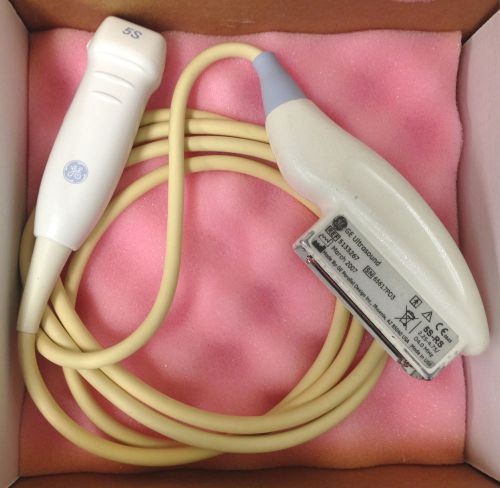

GE 5S-RS Cardiac Sector Transducer Probe For GE Vivid 5S